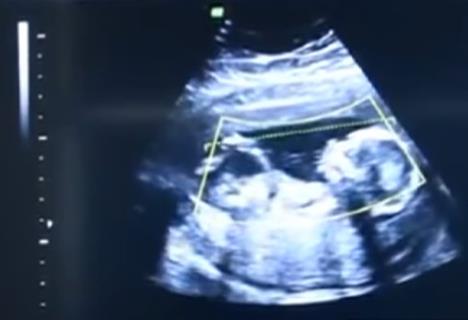

U Sibiru je nedavno zabeležen neverovatan slučaj vanmaterične trudnoće koja se gotovo uvek zavšri iniciranim pobačajem, ali je ovoga puta beba uspela da preživi. Ukrajinska izbeglica iz pokrajine Donbas (31) uspela je da iznese trudnoću bez ijednog odlaska kod lekara na pregled.

Beba je začeta prirodnim putem, ali se nije razvijala u materici, već van nje. Vanmaterične trudnoće poput ove redovno završavaju iniciranim pobačajem ako je rana trudnoća, a čest je slučaj da ženama operativnim putem s plodom moraju da izvade i deo reproduktivnog organa, najčešće jajnik ili jajovod. Do sada je, uz malenu Veroniku, zabeleženo samo 12 takvih slučajeva na svetu.